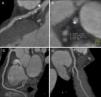

Na aquisição com contraste foi possível excluir doença coronária obstrutiva. Documentou-se a presença de placas mistas, mas predominantemente calcificadas, dispersas por toda a árvore coronária, sobretudo no tronco comum e no segmento proximal da artéria descendente anterior. Foram evidentes placas com remodelagem positiva (Figuras 2 e 3).

AngioTC cardíaca: A – placas predominantemente calcificadas dispersas no segmento proximal da artéria descendente anterior, sem condicionar estenose significativa; B – placa mista, excêntrica, com remodelagem positiva; C e D – artérias circunflexa e coronária direita (vaso dominante) com placas mistas minor, sem estenoses significativas.